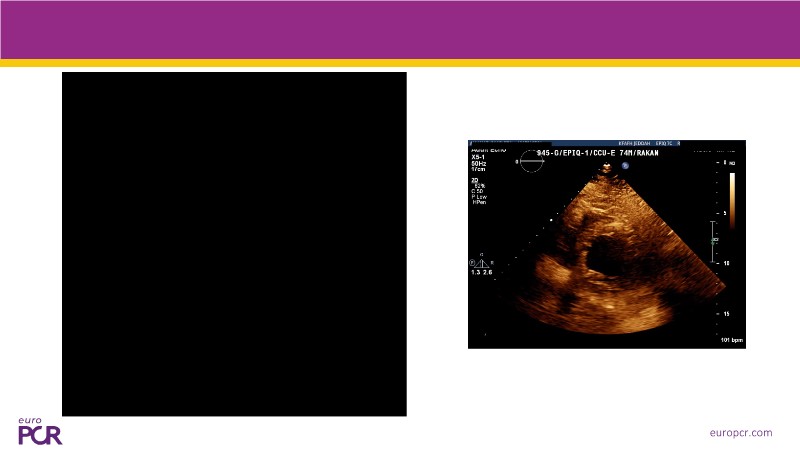

This EuroPCR 2025 session offers a comprehensive update on cardiogenic shock and high-risk PCI, featuring expert analysis of the DanGer-SHOCK and ECLS-SHOCK trials, new insights one year after DanGer-SHOCK, and practical considerations for managing PCI in patients with severely reduced LVEF. Expect to gain a deeper understanding of mechanical support strategies, survival optimisation, and the latest consensus on treating patients unsuitable for surgery.